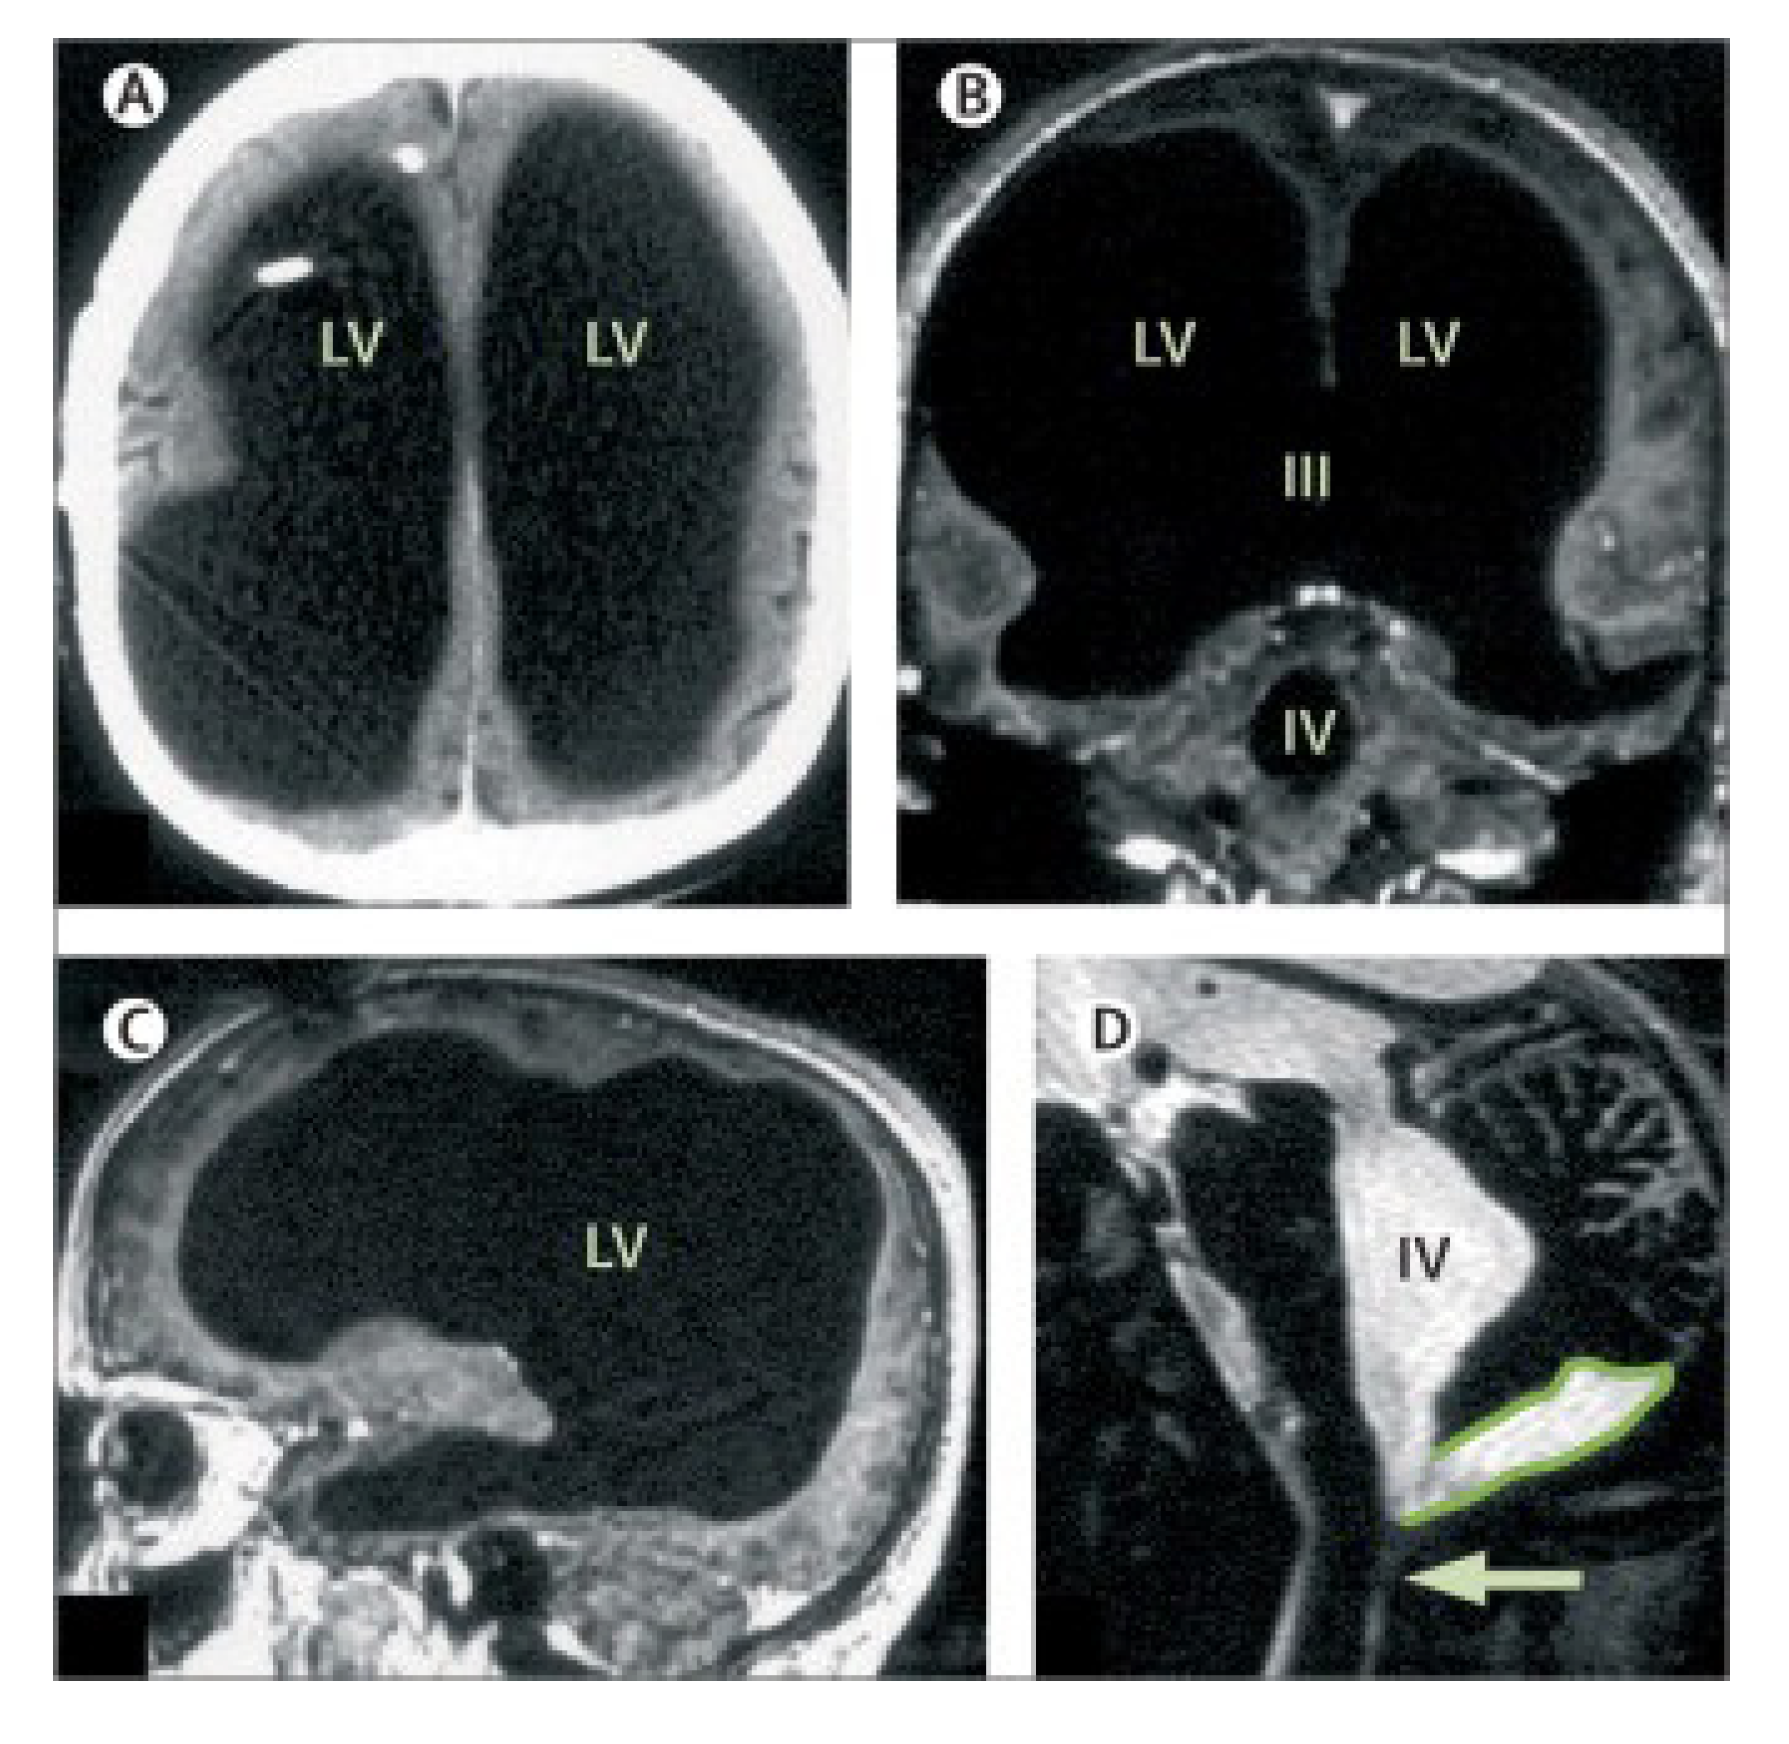

As seen the water is a main liquid medium in the brain where all important events occur. Although dendrites and axon terminals of neurons of the brain penetrate through all brain space everywhere densely, there are spaces relatively free from the nervous filaments. These spaces are ventricles of the brain filled by the cerebral liquid. In medical practice there is a case when a 44-year-old patient with the postnatal hydrocephalus of unknown cause [48] showed by the magnetic resonance imaging (MRI) that his brain has hypertrophied brain ventricles, Figure 14. The deficit of the filamentous organization demonstrates massive enlargement of the lateral, third, and fourth ventricles, with a very thin cortical mantle and a posterior fossa cyst. Surprisingly however, this patient possesses normal social functions, and has an intelligence quotient (IQ) of about 75. This example gives an indirect hint at the fact that the cerebral liquid, a slightly brackish water, has a direct relationship to cognitive functions of the brain.

As the photo Figure 14 shows only a thin layer adjoining the cranial box represents neural tissue. The rest of the space in the skull is occupied by cerebrospinal liquid washing the dendritic processes. It is that case, when the gap junctions washed by the liquid play a crucial role. For comparison, it is suggested to look at Figure 15 showing the horizontal incision of the brain going through the lateral ventricles of the brain. One can see that an area occupied by the ventricles is smaller than those shown in Figure 14. However the liquid filling these ventricles wash the hippocampus from all sides rather tightly. In fact, the left and right hippocampal arcs are fully immersed in the cerebral liquid. Perhaps, a neighborhood of the hippocampus with such a water basin plays a crucial role for its functions, since we know that the water is a source of free protons arising due to thermal fluctuations.

Figure 14. Massive ventricular enlargement, in a patient with normal social functioning: (A), (B), (C) MRI with gadolinium contrast at different cross-sections; (D) T2-weighted MRI. LV=lateral ventricle. III=third ventricle. IV=fourth ventricle. Arrow points to Magendie foramen. The posterior fossa cyst is outlined in (D). The figure is taken from [48] (Open access).